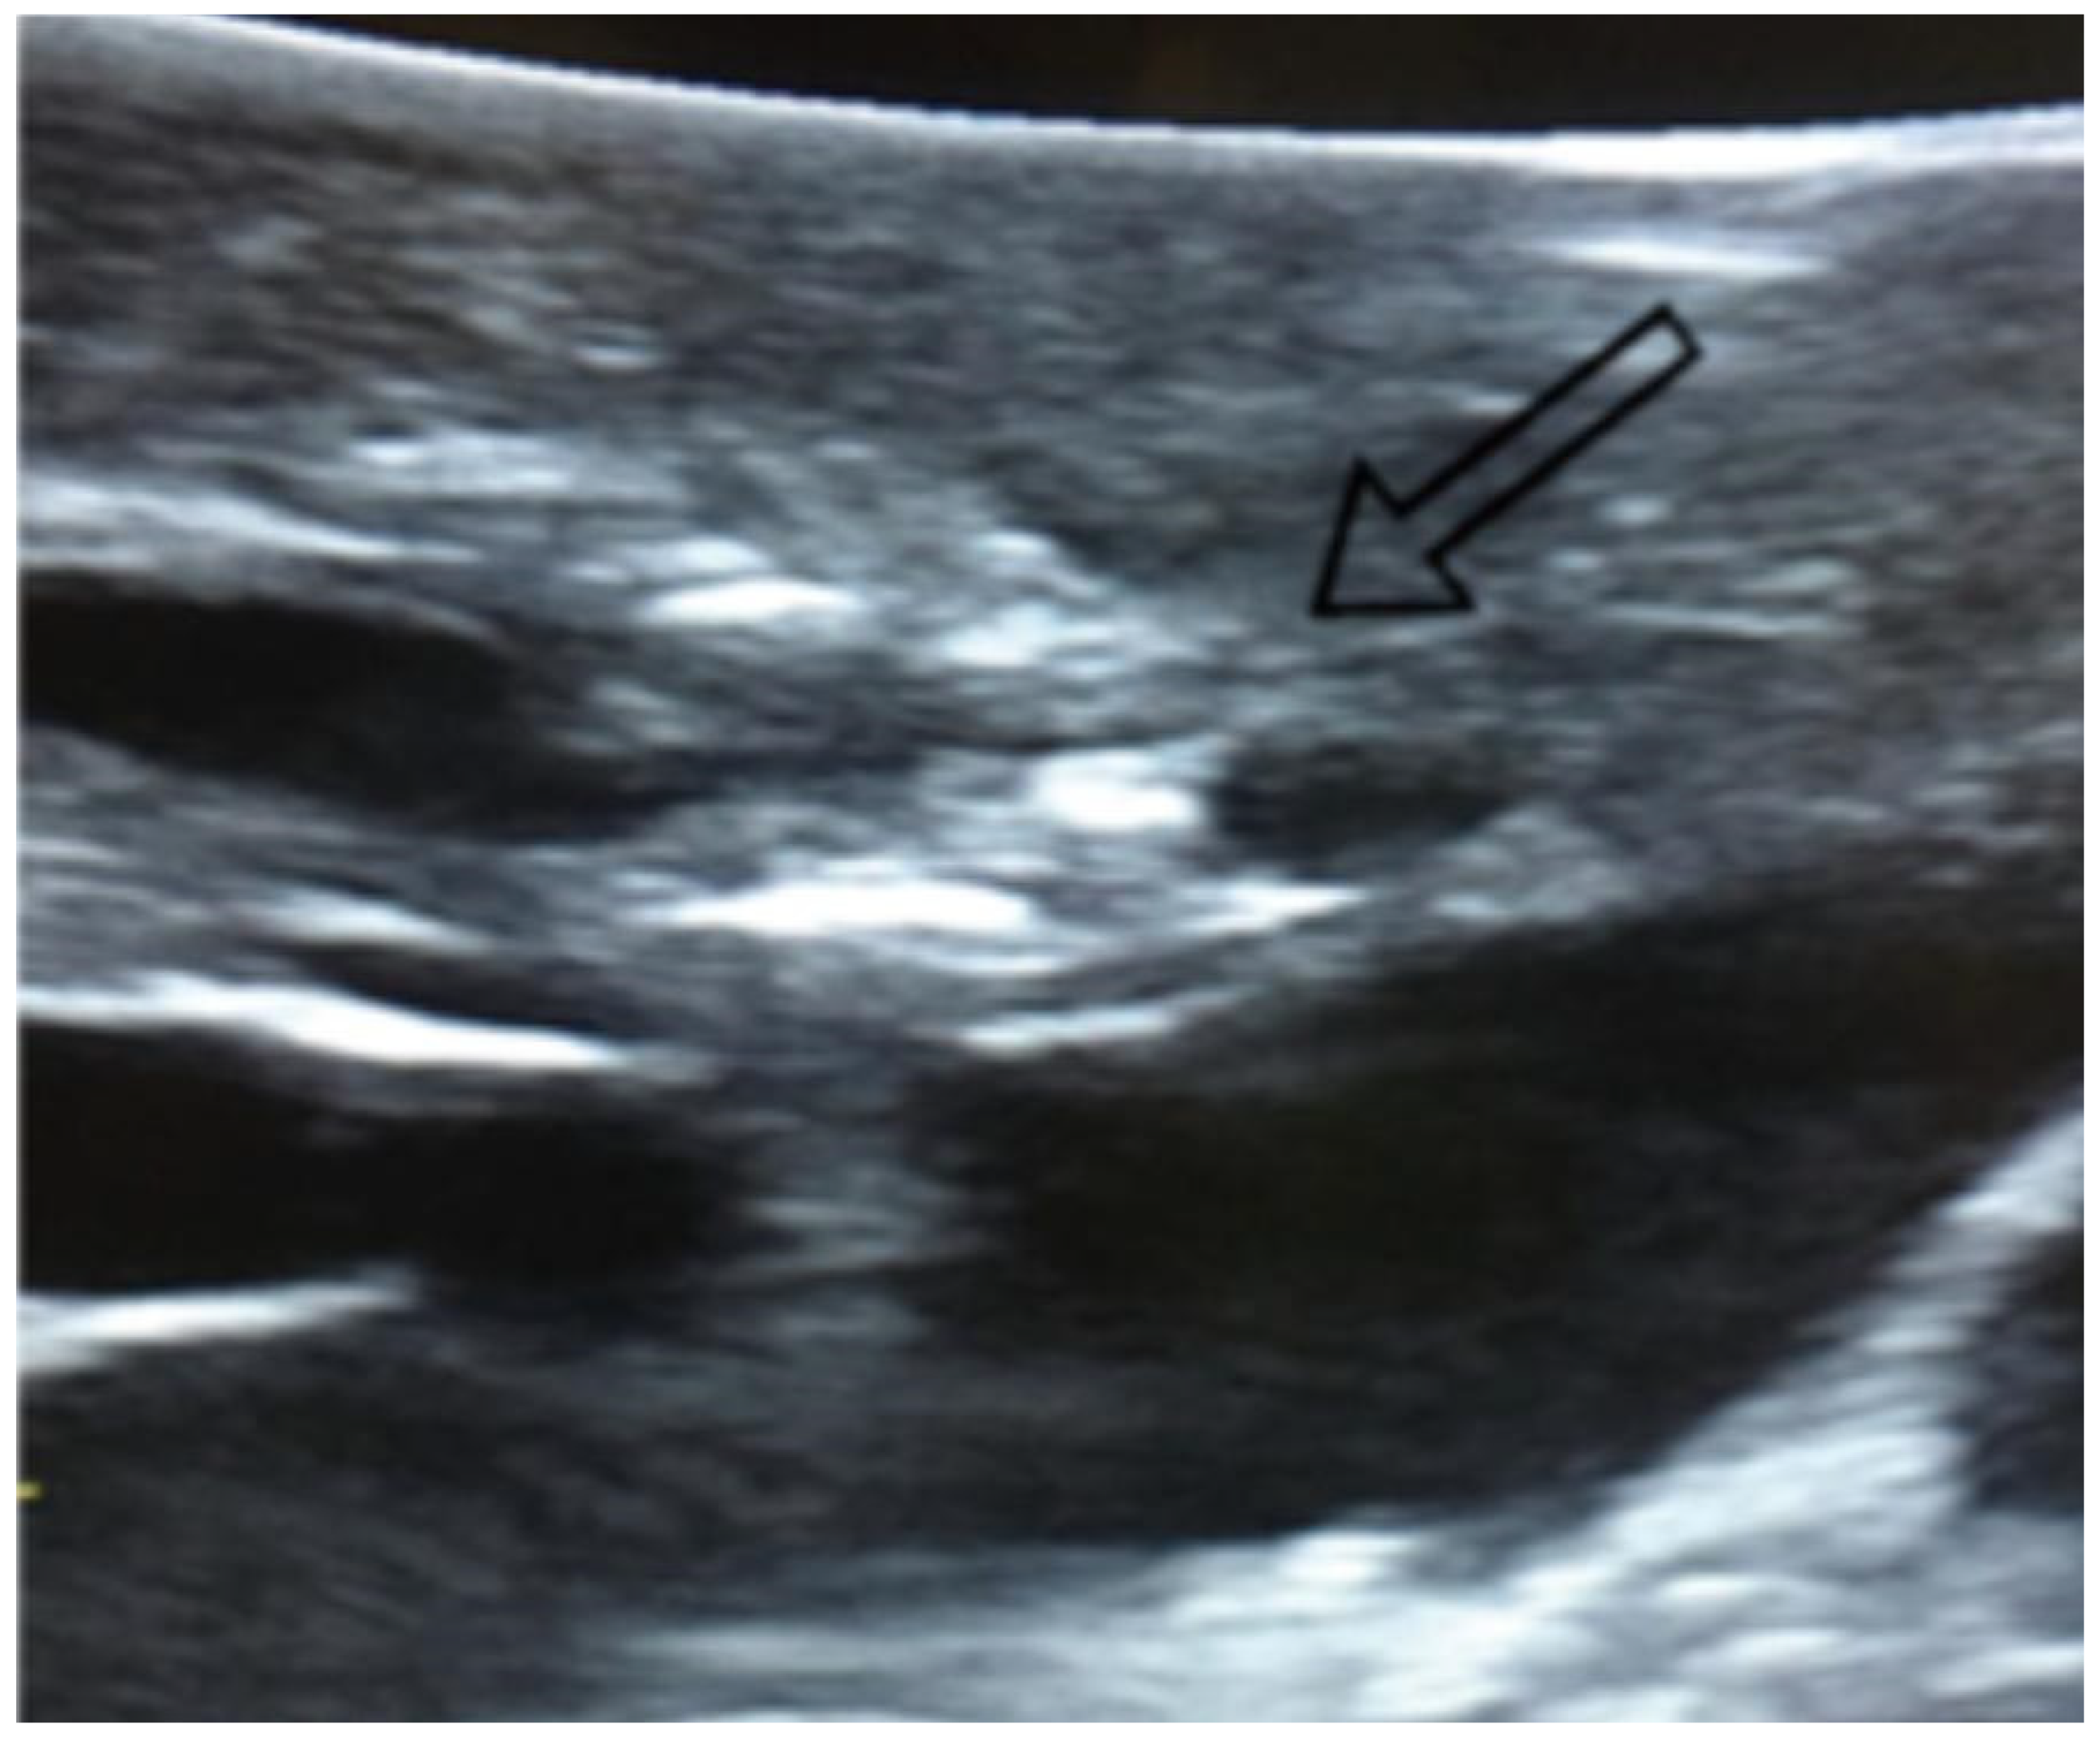

Figure 1.

Visualization of lung nodules on intraoperative lung ultrasound. A pulmonary nodule is seen as a hyperechoic area, as indicated by the arrow.